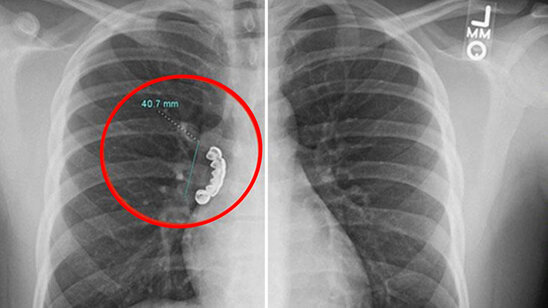

22 yaşlı gəncin protez dişi ağ ciyərinə batdı - FOTO

Amerika Birləşmiş Ştatlarında 22 yaşlı gəncin taxma dişi ciyərinə batıb.

BAKU.WS xarici KİV-ə istinadən xəbər verir ki, Uiskonsin əyalətində yaşayan gənc epilepsiya (beyindəki neyronların anidən və nəzarətsiz şəkildə boşalması) keçirən zaman gümüşdən olan pratezini udub.

Bundan sonra o, şiddətli öskürək və ciyərlərində xışıltı olaması səbəbilə həkimə aparılıb. Orqanları rentgenə salınan zaman ağ ciyərində 4 sm uzunluğunda taxma diş aşkar edilib.

Həkimlər gəncin ağ ciyərindəki protezi çıxarıblar. Müalicələr aparıldıqdan sonra isə o, xəstəxanadan evə buraxılıb.